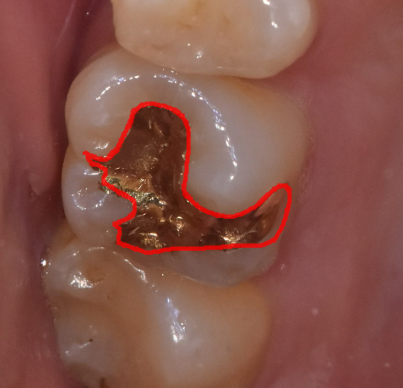

- 충치가 넓고 깊다면? – 인레이와 온레이

충치가 깊거나 크기가 커진 경우에는 레진으로는 부족할 수 있습니다.

이럴 때 사용되는 치료가 바로 인레이와 온레이입니다.

떼우는 형태에 따라 이름이 달라지는 것일뿐

같은 치료인데요~

241028

앞에서 보았던 레진 치료 시 보았던 구멍보다

범위가 넓죠!?

충치가 넓게 퍼져있거나 (가로로)

수직으로 깊게 있지만 신경은 뚫리지 않았을 때 (세로)

시행하고 있습니다.